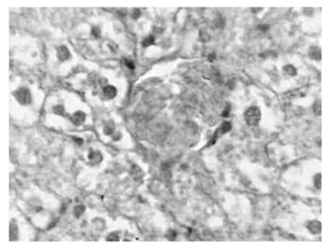

У крыс ОГ-2 в печени выявлены структурные изменения, характеризующиеся чередованием анабо-лических и катаболических реакций. Следует особо отметить, что в печени животных этой группы весьма четко прослеживается тенденция, направленная на восстановление цитоангиоархитектоники органа (рис. 3а). Повсеместно структурная перестройка со-провождалась активацией репаративных процессов. Так, гепатоциты вновь приобретали способность формировать характерные белки, располагались ра-диально по отношению к центральной вене.

На значительном протяжении прослеживались признаки упорядочения структуры органа, прояв-ляющиеся в наличии многочисленных печеночных долек.

Необходимо отметить и следующее обстоятельство. В участках, в которых четко прослеживаются репаративные процессы вокруг центральной вены и микрососудов триад, выявляются умеренные клеточные инфильтраты, представленные преимущественно клетками лимфоцитарного и макрофагального ряда (рис. 3б). Подобная клеточная реакция нами была зарегистрирована только в ОГ-2. Учитывая характер клеточного инфильтрата, не исключено, что в условиях введения подопытным животным L-аргинина происходит структурная перестройка печени, сопро-вождающаяся процессами модуляции региональных иммунологических реакций. В пользу данного обстоятельства, правда косвенно, свидетельствуют и литературные данные, согласно которым L-аргинин. дозозависимым путем оказывает избирательное модулирующее влияние на иммунокомпетентные клетки - в плане направленной активации синтеза антивоспалительных цитокинов [11, 12]. На основании полученных нами морфологических результатов, не представляется возможным в должной мере оценить биологическую значимость данного факта. С этой целью необходимо провести специальные иммуномор- фологические и иммуноферментные исследования, направленные на установление принадлежности обнаруженных в клеточном инфильтрате лимфоцитов к Т и/или В популяциям. Только, после проведения указанных исследований представится возможным в должной степени оценить биологическую значимость установленного нами факта - в плане роли ре-гиональных иммунологических реакций в восстано-вительных процессах в печени животных ОГ-2.

Рис. 3. Структурные сдвиги в печени подопытных животных, подвергнутых ишемии, в условиях введения L-аргинина. ОГ-2. Гематоксилин-эозин.

а. Четко прослеживается тенденция, направленная на восстановление структурной организации смежных печеночных долек. Гепатоциты вновь приобретают способность формировать характерные балки. Признаки умеренной периваскулярной клеточной инфильтрации. Об. 10, ок. 10.

б.Выраженная клеточная лимфоцитарная и макрофагальная инфильтрация стромы в регионе микро-сосудов триад печени. Об. 40, ок. 10.